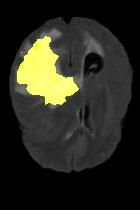

Current unsupervised anomaly localization approaches rely on generative models to learn the distribution of normal images, which is later used to identify potential anomalous regions derived from errors on the reconstructed images. However, a main limitation of nearly all prior literature is the need of employing anomalous images to set a class-specific threshold to locate the anomalies. This limits their usability in realistic scenarios, where only normal data is typically accessible. Despite this major drawback, only a handful of works have addressed this limitation, by integrating supervision on attention maps during training. In this work, we propose a novel formulation that does not require accessing images with abnormalities to define the threshold. Furthermore, and in contrast to very recent work, the proposed constraint is formulated in a more principled manner, leveraging well-known knowledge in constrained optimization. In particular, the equality constraint on the attention maps in prior work is replaced by an inequality constraint, which allows more flexibility. In addition, to address the limitations of penalty-based functions we employ an extension of the popular log-barrier methods to handle the constraint. Comprehensive experiments on the popular BRATS'19 dataset demonstrate that the proposed approach substantially outperforms relevant literature, establishing new state-of-the-art results for unsupervised lesion segmentation.

翻译:目前未受监督的异常本地化方法依靠基因模型来了解正常图像的分布,这些模型后来被用于确定从重建图像错误中得出的潜在异常区域。然而,几乎所有先前文献的主要局限性是,需要使用异常图像来设定一个特定等级的阈值以定位异常。这限制了其在现实情景中的可用性,在现实情景中,只有通常能获取正常数据。尽管存在这一重大缺陷,但只有少数作品通过在培训中整合对关注地图的监督,解决了这一局限性。在这项工作中,我们提议了一种新颖的提法,不要求使用异常图像来界定阈值。此外,与最近的工作相反,拟议的限制是以更加有原则的方式拟订的,在限制优化时利用众所周知的知识。特别是,先前工作中对关注地图的平等性制约被一种不平等性制约所取代,这允许更大的灵活性。此外,为了解决基于惩罚的功能的局限性,我们采用了流行的日志障碍方法来应对这一制约。我们建议对流行的BRATS'19数据设置进行综合实验,这与最近的工作不同,因此,拟议的限制是以更加有原则的方式提出了限制,即拟议的方法大大地超越了相关的分段结果。